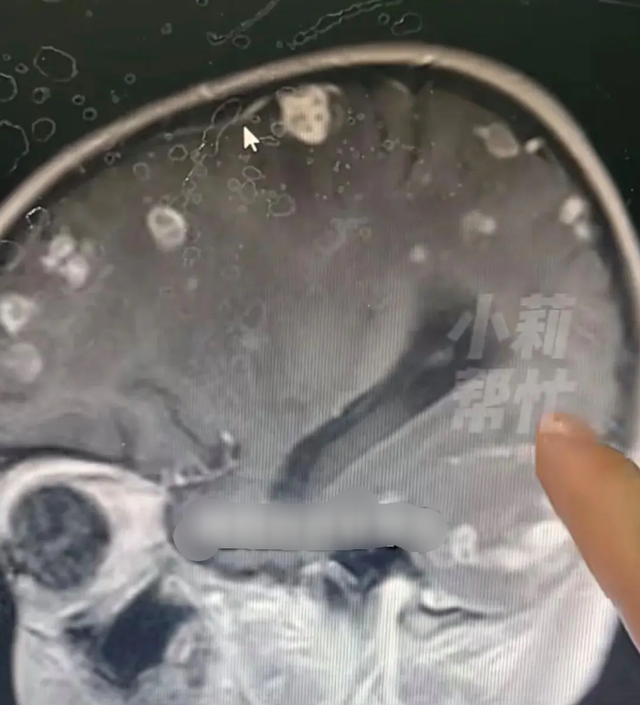

Một bé gái 6 tuổi ở Trung Quốc bị sốt kéo dài suốt 17 ngày. Sau khi kiểm tra, bác sĩ phát hiện não của em xuất hiện hơn 20 ổ tổn thương, như thể bị “gặm nhấm”.

Theo Đài Phát thanh – Truyền hình Hà Nam, chương trình “Tiểu Lị Giúp Đỡ” đưa tin, mới đây tại Trịnh Châu (Hà Nam), một bé gái 6 tuổi bị sốt kéo dài suốt 17 ngày. Sau khi kiểm tra, bác sĩ phát hiện não của em xuất hiện hơn 20 ổ tổn thương, như thể bị “gặm nhấm”.

Phó trưởng khoa Hồi sức tích cực Nhi khoa, Bệnh viện trực thuộc số 1 Đại học Trịnh Châu – bác sĩ Hoắc Ngọc Phong cho biết, nguyên nhân là do nhiễm nấm Aspergillus fumigatus (nấm khói).

Thời điểm đó, bé theo gia đình về một căn nhà cũ đã bỏ trống lâu ngày để dọn dẹp. Trong thời gian ngắn, bé hít phải lượng lớn bụi mốc tích tụ trong nhà, khiến nấm xâm nhập vào máu và lan lên não.